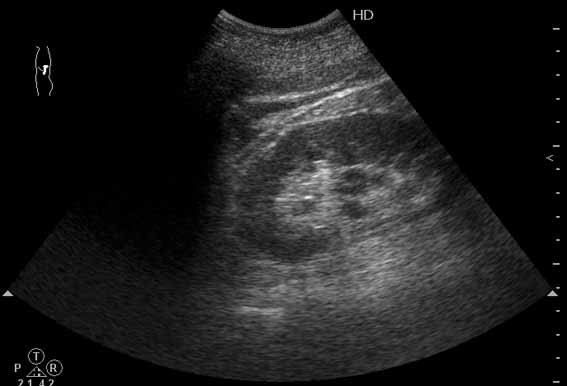

Изменения забрюшинного пр-ва при о.панкреатите (УЗИ)

Мужчина средних лет с болями в животе.

Сонограмма выполнена из левого поясничного доступа.

О каком заболевании нужно подумать в первую очередь по такой картинке?

На фоне незначительно дилатированной верхней чашки мелкое гиперэхогенное включение без четкой уз тени.Смею предположить МКБ, не могу рассмотреть гипоэхогенные включения в центре почечного синуса м.б. это паренхима?

Согласен с коллегой. Это может быть МКБ, в том числе, и с камнем в мочеточнике (с мочевой дорожкой) - отсюда боли.

Немного пофантазировав, здесь можно увидеть и небольшую кисту почечного синуса, и папиллярные разрастания и даже мягкий конкремент.

Друзья, вы увлеклись изучением почки. Реально в почке ничего существенного нет. Еще раз просмотрите видео.

Наводящий вопрос: что это (стрелка)?